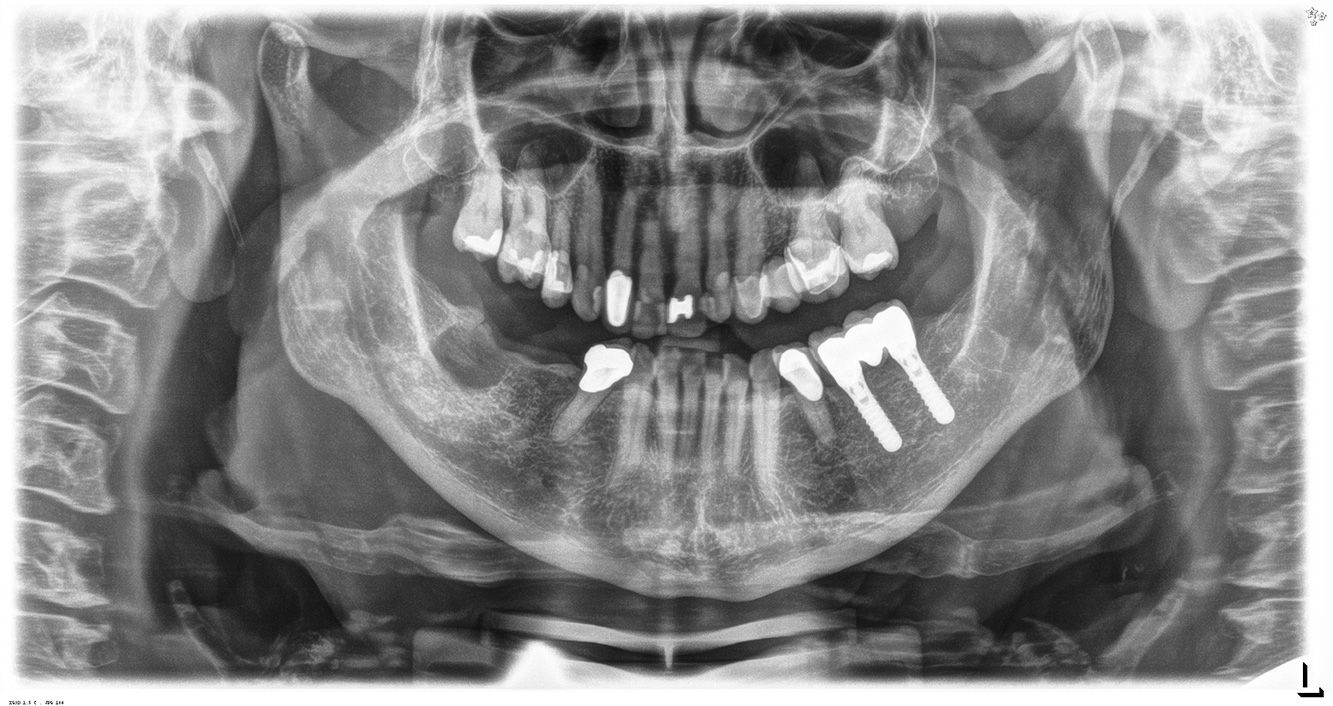

In the medical history, the 55-year-old patient states that he has no systemic disease and is not taking any medication. The patient’s lifestyle is similarly unremarkable. The patient has a few tooth restorations and two implants (2nd and 4th quadrants). On the basis of current findings, gingivitis is identified in an otherwise stable periodontal condition on the reduced periodontium (stage III, grade A). more

The healthy patient with pre-existing periodontal disease & peri-implantitis

A 52-year-old patient presents at a preventive care session. The patient has no systemic disease and is not taking any medication. He has had various dental treatments and also has two active carious lesions. In addition, the patient has four implants (2nd, 3rd and 4th quadrants). He is revealed to have early periodontal disease (stage IV, grade B). His periodontal condition is stable; a probing depth of Probing depths (ST) of 5 mm is only evident at the implant in region 36. Gingivitis is also identified. more

The healthy patient with early periodontal disease